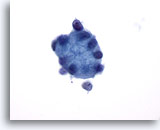

Figure 16

Breast FNA, Breast cyst.

This cluster of benign ductal cells shows mild atypia in the form of visible nucleoli and slight nuclear enlargement. Such minimal changes are often noted in breast cyst fluids. 60x

Figure 16

Breast FNA, Breast cyst.

This cluster of benign ductal cells shows mild atypia in the form of visible nucleoli and slight nuclear enlargement. Such minimal changes are often noted in breast cyst fluids.

60x